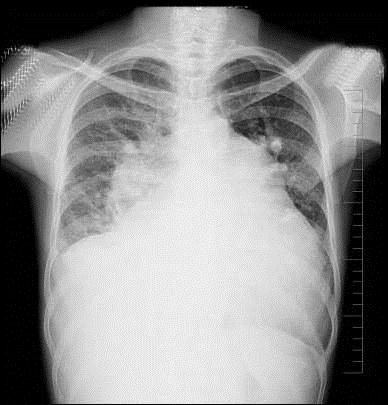

问题 47岁女性患者,诊断风湿性二尖瓣狭窄3年余,近来呼吸困难,咳泡沫痰,拍胸部正位片如图所示,下列关于肺部描述和结论正确的是 ( )

选项 A、肺野透亮度减低 B、考虑肺淤血 C、双侧上下肺静脉比例倒置 D、肺门影模糊 E、双侧肺纹理增强

答案 ABCDE